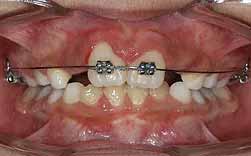

Um diastema interdentário é um espaço exagerado entre as coroas de dois dentes, na sequência normal de erupção. A sua origem pode ser:

Os diastemas revelam-se a partir dos 6 anos, com a erupção dos incisivos.